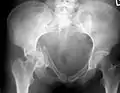

Рентгеновский снимок перелома правой тазовой кости с повреждением вертлужной впадины суставной головкой бедренной кости